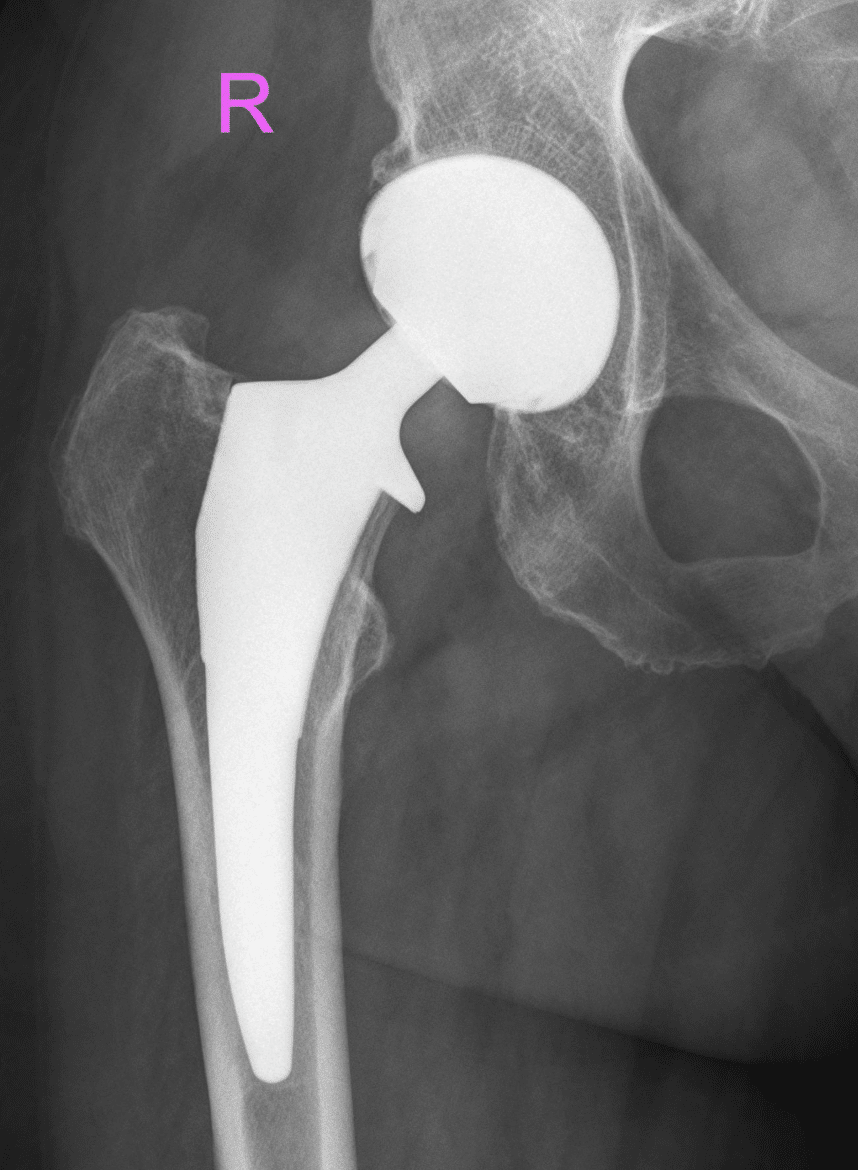

Der Gelenkersatz stellt in der orthopädischen Chirurgie eine bewährte Option dar, wenn konservative Behandlungsmethoden wie Physiotherapie, medikamentöse Schmerztherapie oder Infiltrationen keine ausreichende Linderung mehr erzielen. Er kommt bei fortgeschrittener Arthrose oder ausgeprägten Gelenkschäden zum Einsatz, um die Beweglichkeit wiederherzustellen und Schmerzen nachhaltig zu reduzieren. In der Endoprothetik werden künstliche Gelenke eingesetzt, um die Funktion des erkrankten oder zerstörten Gelenks langfristig zu ersetzen.

Die Endoprothetik umfasst ein präzise abgestimmtes operatives Vorgehen, bei dem geschädigte Gelenkflächen entfernt und durch hochwertige Implantate ersetzt werden. Dabei werden individuell angepasste Prothesenmodelle verwendet, die sowohl anatomische Gegebenheiten als auch die funktionellen Anforderungen des Gelenks berücksichtigen. Der Eingriff erfolgt unter muskelschonenden Bedingungen, häufig unter Verwendung minimalinvasiver Techniken, um Weichteilverletzungen zu vermeiden und die postoperative Rehabilitation zu beschleunigen.

Durch intraoperative Bildgebung und computergestützte Navigation kann die exakte Positionierung der Prothese sichergestellt werden, ein entscheidender Faktor für langfristige Stabilität, natürliche Bewegungsabläufe und den dauerhaften Erfolg des Gelenkersatzes.